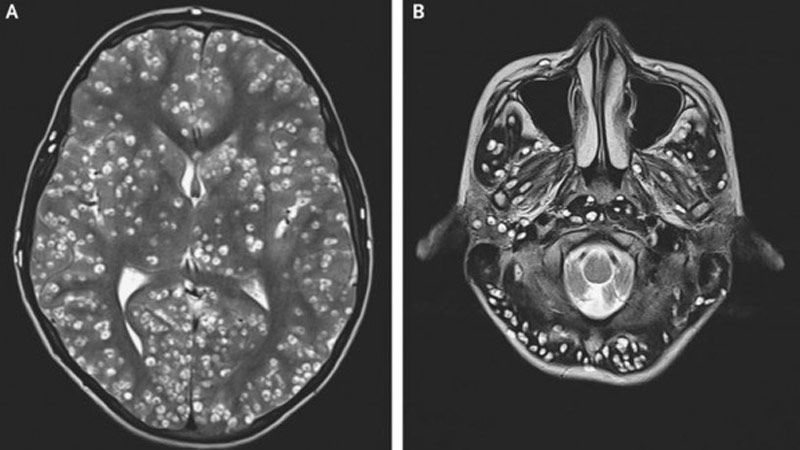

"La resonancia magnética mostró numerosas lesiones quísticas bien definidas en toda la corteza cerebral y el tronco encefálico y el cerebelo que eran compatibles con la neurocisticercosis", señalan los médicos doctores Nishanth Dev y S. Zafar Abbas, del Colegio Médico y Hospital ESIC en Faridabad.